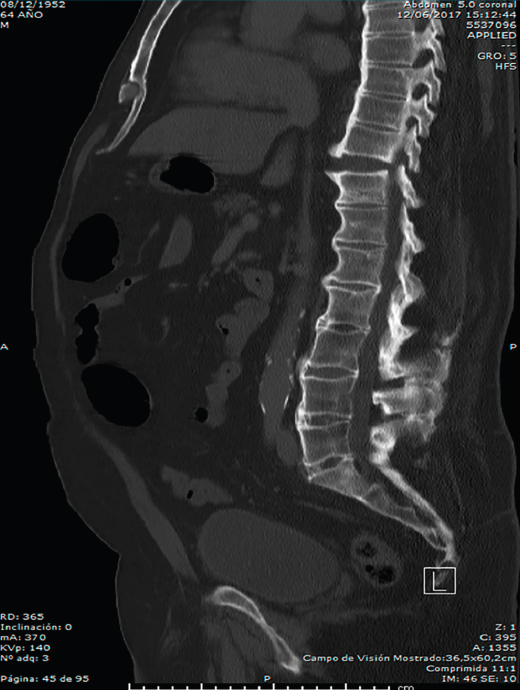

Se puede observar con más claridad la lesión traumática T10/T11 y la sindesmofitosis de todo el raquis en el corte sagital de una tomografía axial computarizada de cuerpo (body TAC) (Figura 2).

Figura 2. Corte sagital de tomografía axial computarizada dorsolumbar.